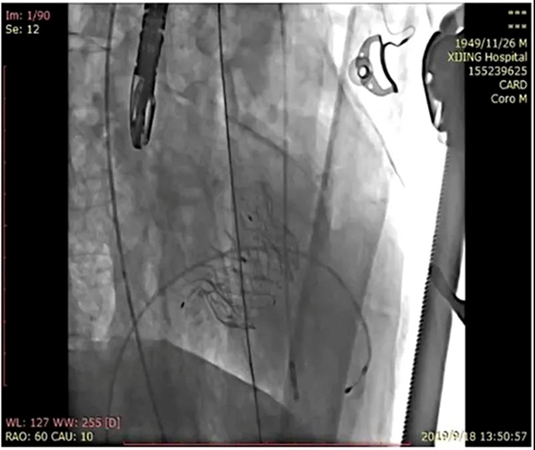

Mi-thos®成功释放